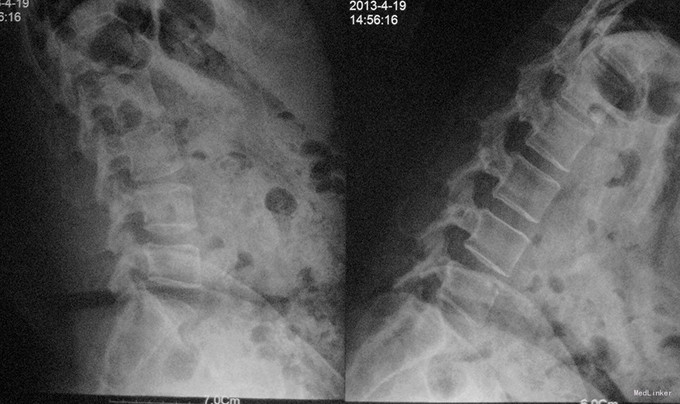

查体:脊柱生理弯曲存在,腰椎活动受限,L4/L5棘突压痛叩痛,叩击痛。双侧直腿抬高试验(-)。双下肢皮肤感觉正常,双侧髂腰肌、股四头肌、双侧胫前肌、踇背伸肌肌力Ⅳ级,腹壁反射、肛门反射正常,两侧膝正常,双侧踝反射未引出。双侧Babinski征(-),双侧皮温及色泽正常,双侧足背动脉搏动良好。 辅助检查:X光片示:动力位片显示腰椎4/5椎间失稳。MRI检查显示:腰4/5椎间盘突出,黄韧带肥厚致椎管狭窄,相应节段硬膜囊受压改变。

诊断:腰4/5椎管狭窄并失稳症。 治疗:给予行后路腰4/5右侧椎板间开窗减压椎间盘摘除并肥厚黄韧带切除+棘突间wallis固定术。